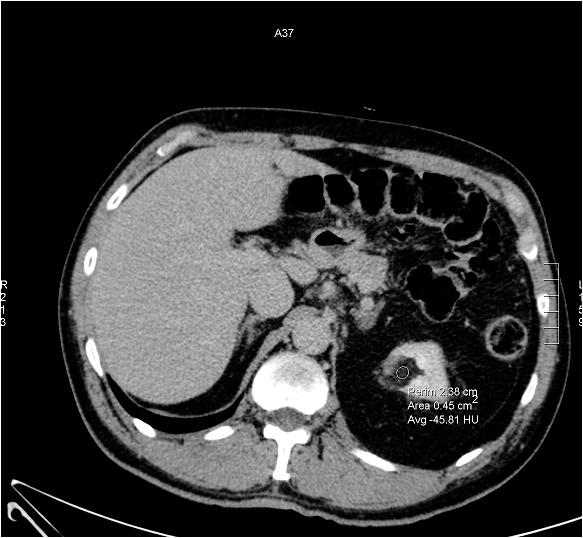

Angiomyolipoma is a hamartoma which is primarily composed of fat, vessels and smooth muscle. It is most common in females in their forties. Compared to other renal lesions the fat content is considered specific for this tumor, and it can be easily detected on imaging studies.

Image

Figure 4. Angiomyolipoma (well circumscribed hyperechoic mass) US image

On the CT scan the fat content is highlighted as a typically hypodense area, where negative HU values can be detected.

Figure 5. Hypodense (fat containing) well circumscribed mass: CT morphology is consistent with angiomyolipoma.